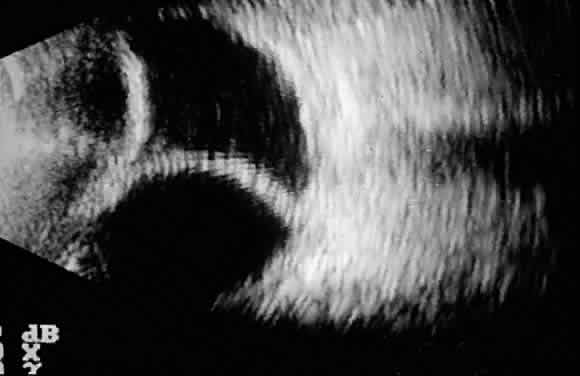

The initial management of early postoperative hypotony with a formed anterior chamber is conservative. Topical steroids and cycloplegics are used. Restrictions in activity (bending, weight lifting) and avoidance of Valsalva-positive conditions are recommended, especially in patients at risk for suprachoroidal hemorrhage (see earlier). If there is hyposecretion related to intraocular inflammation, ciliochoroidal detachment, or both, the initial treatment consists of intense corticosteroid therapy and long-acting cycloplegics, which stabilize the blood-aqueous barrier. Intervention is indicated in patients with hypotony associated with other complications and in persistent, low IOP with loss of visual acuity and hypotony maculopathy. After filtration surgery, prompt management is indicated, also when there is loss of bleb height. Treatment should be aimed at correcting the specific cause of hypotony. When there is lens-corneal touch (flat anterior chamber, grade III) immediate surgical intervention is necessary to prevent endothelial damage and cataract formation (see Chapter 15). Reformation of the anterior chamber with air, balanced salt solution, or, preferably, a viscoelastic can be done at the slit lamp or under the operating microscope through the paracentesis made intraoperatively. Viscoelastic material is best for maintaining, at least temporarily, the anterior chamber depth. When there are large and appositional choroidal effusions, drainage of the fluid also is necessary (Fig. 4). The technique is described in detail in Chapter 15.

Fig. 4. B-scan ultrasound showing hyperreflective dome-shaped echoes corresponding to the detached choroid-retina, with acoustically hollow content corresponding to the fluid accumulated in the suprachoroidal space.